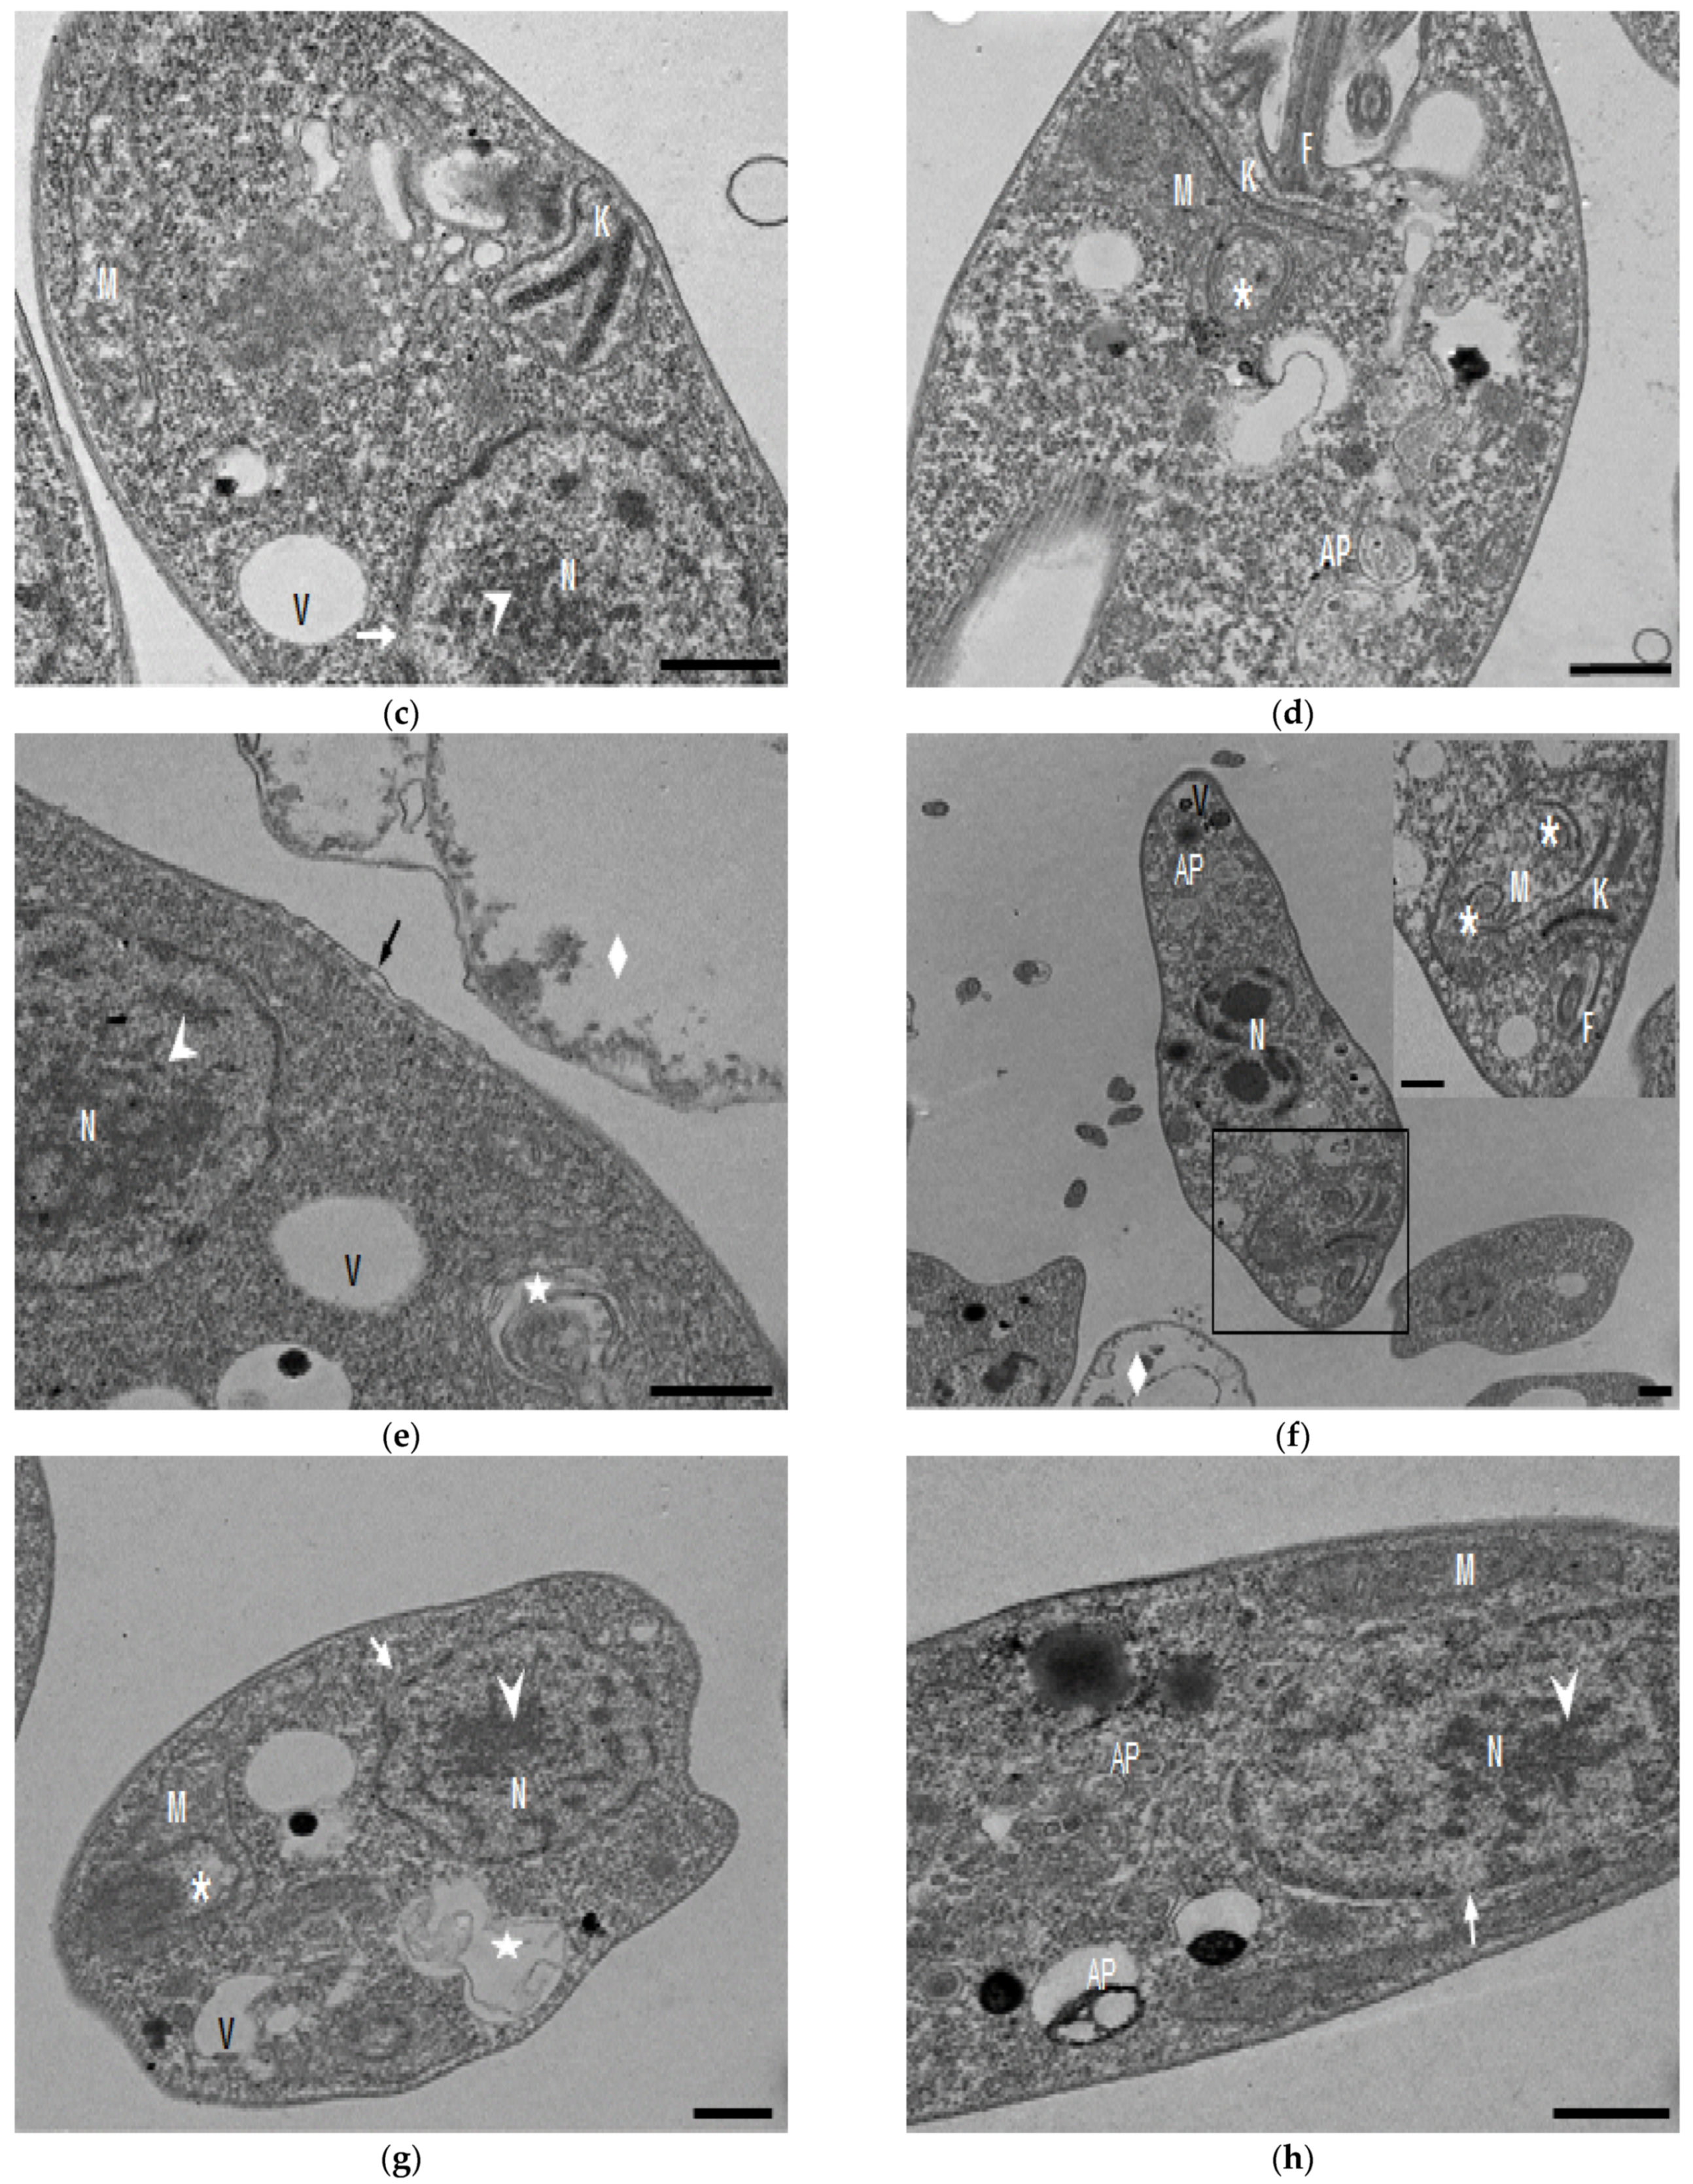

Compound 8 induced several ultrastructural changes in L. mexicana promastigotes, as evidenced by SEM (Figure 1). SEM analysis of the non-treated parasites showed a typical elongate morphology of promastigotes with their anterior flagella (Figure 1a); meanwhile, the treated parasites showed a rounded shape (Figure 1b–e), profound alterations in their membranes (Figure 1b–d), membrane blebbing (Figure 1b,d,e) and flagella length reduction as well as a bulbous structure at the flagella tip (Figure 1b–e).

Figure 1.

SEM analysis of L. mexicana promastigotes: non-treated (a) or treated with compound 8 at 3.2 µM for 6 h (b,c) and 12 h (d,e). Control promastigotes show the typical morphology (a). Treated parasites show distorted shapes, surface damage (b–d) (asterisk), modification to the flagella tip (arrowhead) (b,c), shortened flagella (arrow) (d,e) and membrane blebbing (star) (b,d,e). (bar = 2 µm). magnification × 8000.

In the present study, with an interest in continuing the characterization of compound 8’s leishmanicidal activity, SEM studies were performed. It was demonstrated that compound 8 induced important ultrastructural changes in L. mexicana promastigotes such as membrane blebbing resembling an apoptotic-like process [20] and alterations in the flagella structure. In addition, TEM studies revealed alterations in the kinetoplast structure and profound mitochondrion damage including swelling and the presence of concentric membranes inside the organelle. We also observed cytoplasmic myelin-like figures indicative of an autophagy process, among other changes. Similar findings were described when L. amazonensis promastigotes were treated with Miltefosine [20], antifungal azoles [21] and calpains inhibitors [22]. In trypanosomastids, severe mitochondrion damage as well as an intense autophagy process and subsequent apoptosis cell death was related to a significant increase in reactive oxygen and nitrogen species (ROS and RNS) [23]. Parasites are exposed to extracellular ROS during their entire life cycle in the insect vector, as well as during the invasion of mammalian host cells [24], but ROS are also produced within the parasite through its electron transport chain or drug detoxification. In the present study, it was demonstrated that compound 8 triggers the production of ROS and parasite apoptosis, indicating that intracellular ROS production induced with compound 8 could be related to mitochondrial damage, as well as membrane blebbing and myelin-like figures observed in the SEM and TEM studies. Parasite apoptosis induced with compound 8 was demonstrated in the flow cytometry studies.